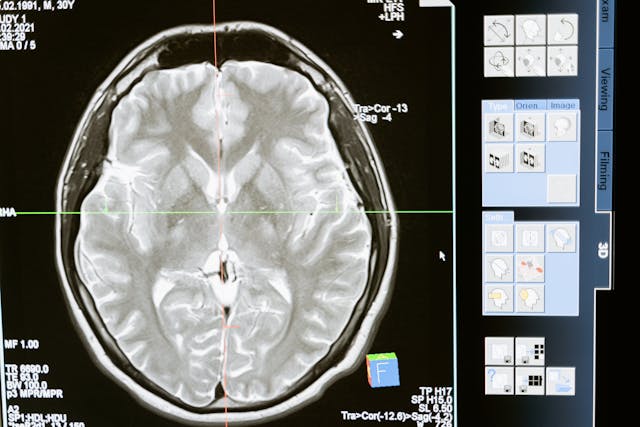

Dans le domaine médical, les services d’imagerie, de biologie et de pharmacie sont souvent les plus avancés mais l’IA est aussi très implantée en anesthésie, chirurgie ou médecine.